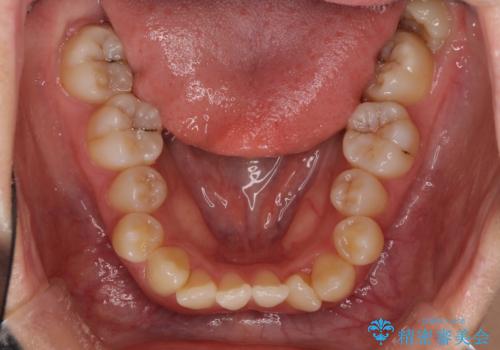

- 上顎の重なっている前歯を気にして来院された患者様です。

重なっている部分は抜歯が必要で、歯の移動量が多く、更には右側にずれている正中を改善する必要がありました。

インビザライン単体での治療は困難と判断し、補助装置により八重歯移動後にインビザラインを用いることとしました。